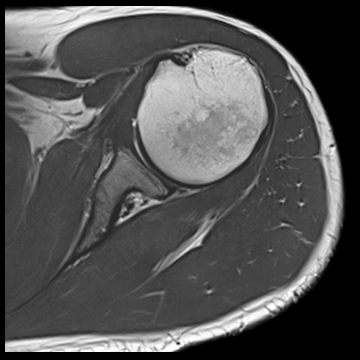

肩関節

T1 TSE FatSat,

T2 TSE FatSat,

T2 TSE,